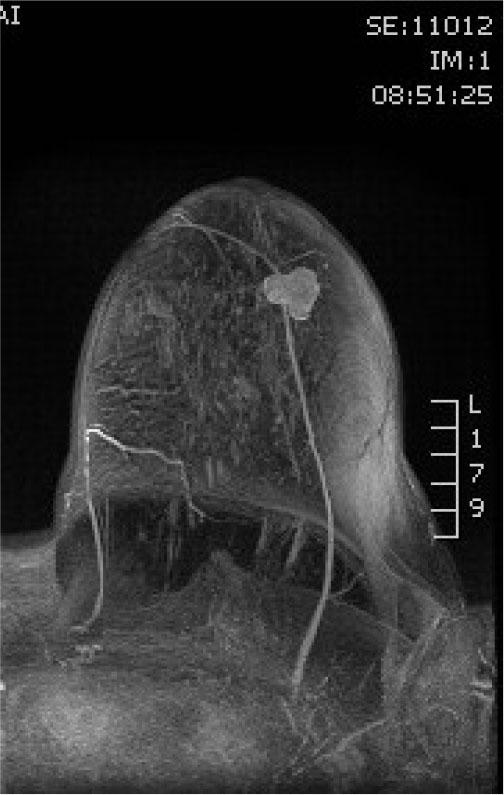

Axial poscontrast T1W section showing hiperintense, lobulated tumor mass

MIP poscontrast reconstruction axial plane showing tumor mass neovascularisation

The review was supplemented by MRI examination, which showed retro and paramamilar tumor mass, in the lower outer quadrant, mixed signal intensity (SI) in T2W / STIR sequences, decreased SI in T1W sequence, postcontrast elevated SI, dynamic characteristics of rapid “wash in”, with a curve of plateau type with few oval shaped lymph up to 10 mm, classified as BIRADS 4 (Figures 2,3,4). Differential diagnostic could correspond to fibroadenoma or fibroadenoma like lesions (FA like lesion). CNB was performed under ultrasound control under local anesthesia and three samples were taken.